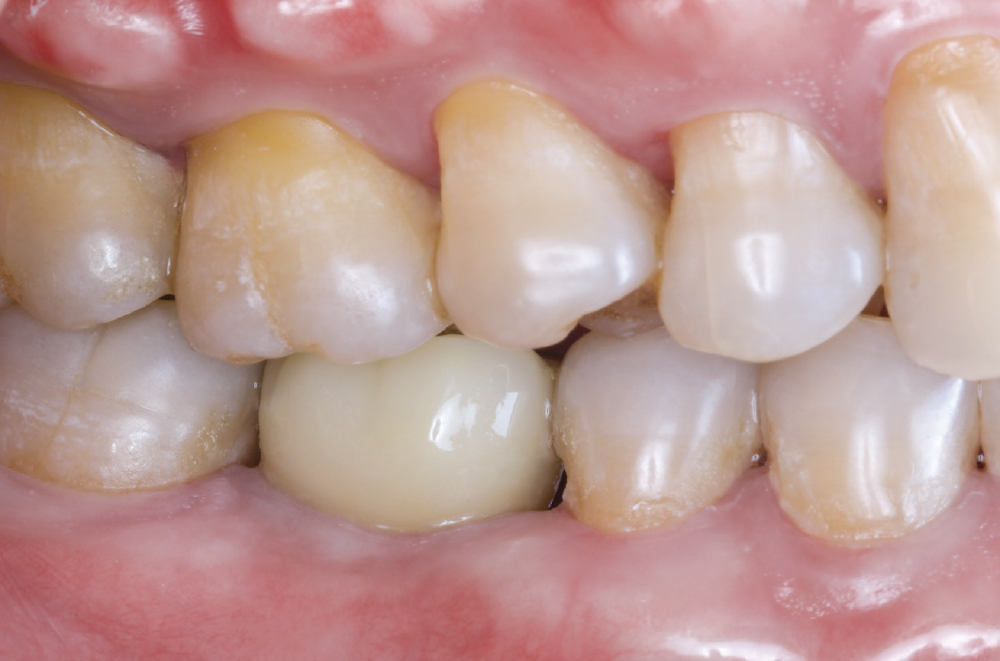

Implant post in socket

Finished Implant Restoration